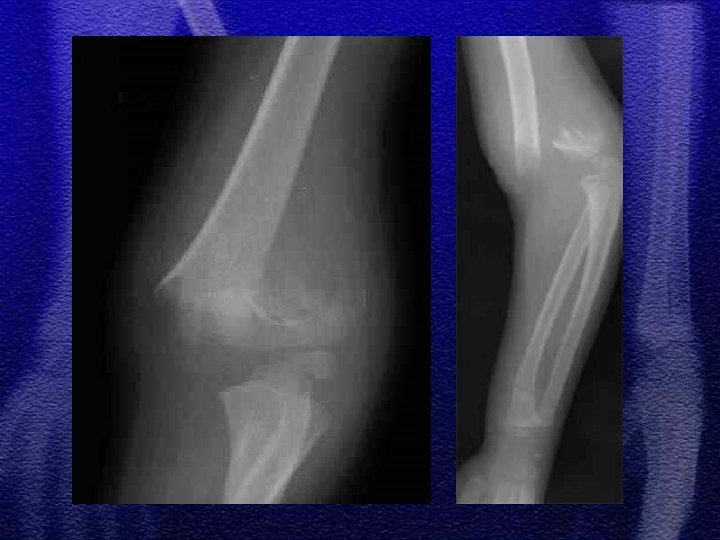

1. Szczyt występowania złamania 3 -10 rok życia, co wynika z budowy anatomicznej, która predysponuje do ww. złamań 2. Wiotkość torebki stawowej i więzadeł usposabia do przeprostu 3. Linia złamania przebiega w przynasadzie w miejscu jej ścieńczenia (dół dla wyrostka dziobiastego oraz wyrostka łokciowego )

§ Wyprostne - 95% § Zgięciowe - 5% § Klasyfikacja wg Gartlanda

§ Repozycja zamknięta , unieruchomienie gipsowe § Repozycja zamknięta i zespolenie przezskórne dwoma drutami Kirschnera § Repozycja otwarta i zespolenie dwoma drutami Kirschnera skrzyżowanymi lub równoległymi § Wyciąg szkieletowy typu „Zeno”

§ Złamania otwarte § Złamania powikłane uszkodzeniem naczyń i nerwów § Niemożność utrzymania poprawnego ustawienia odłamów